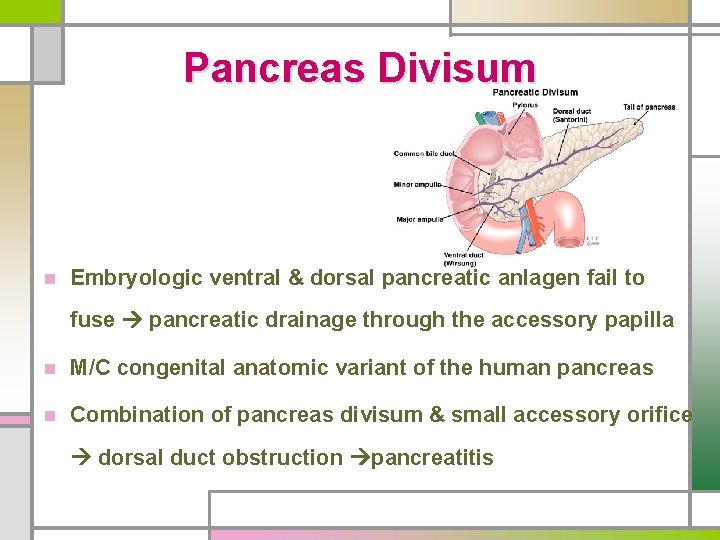

Pancreas Divisum n Embryologic ventral & dorsal pancreatic anlagen fail to fuse pancreatic drainage through the accessory papilla n M/C congenital anatomic variant of the human pancreas n Combination of pancreas divisum & small accessory orifice dorsal duct obstruction pancreatitis